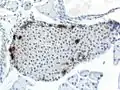

A pancreatic islet, stained. -